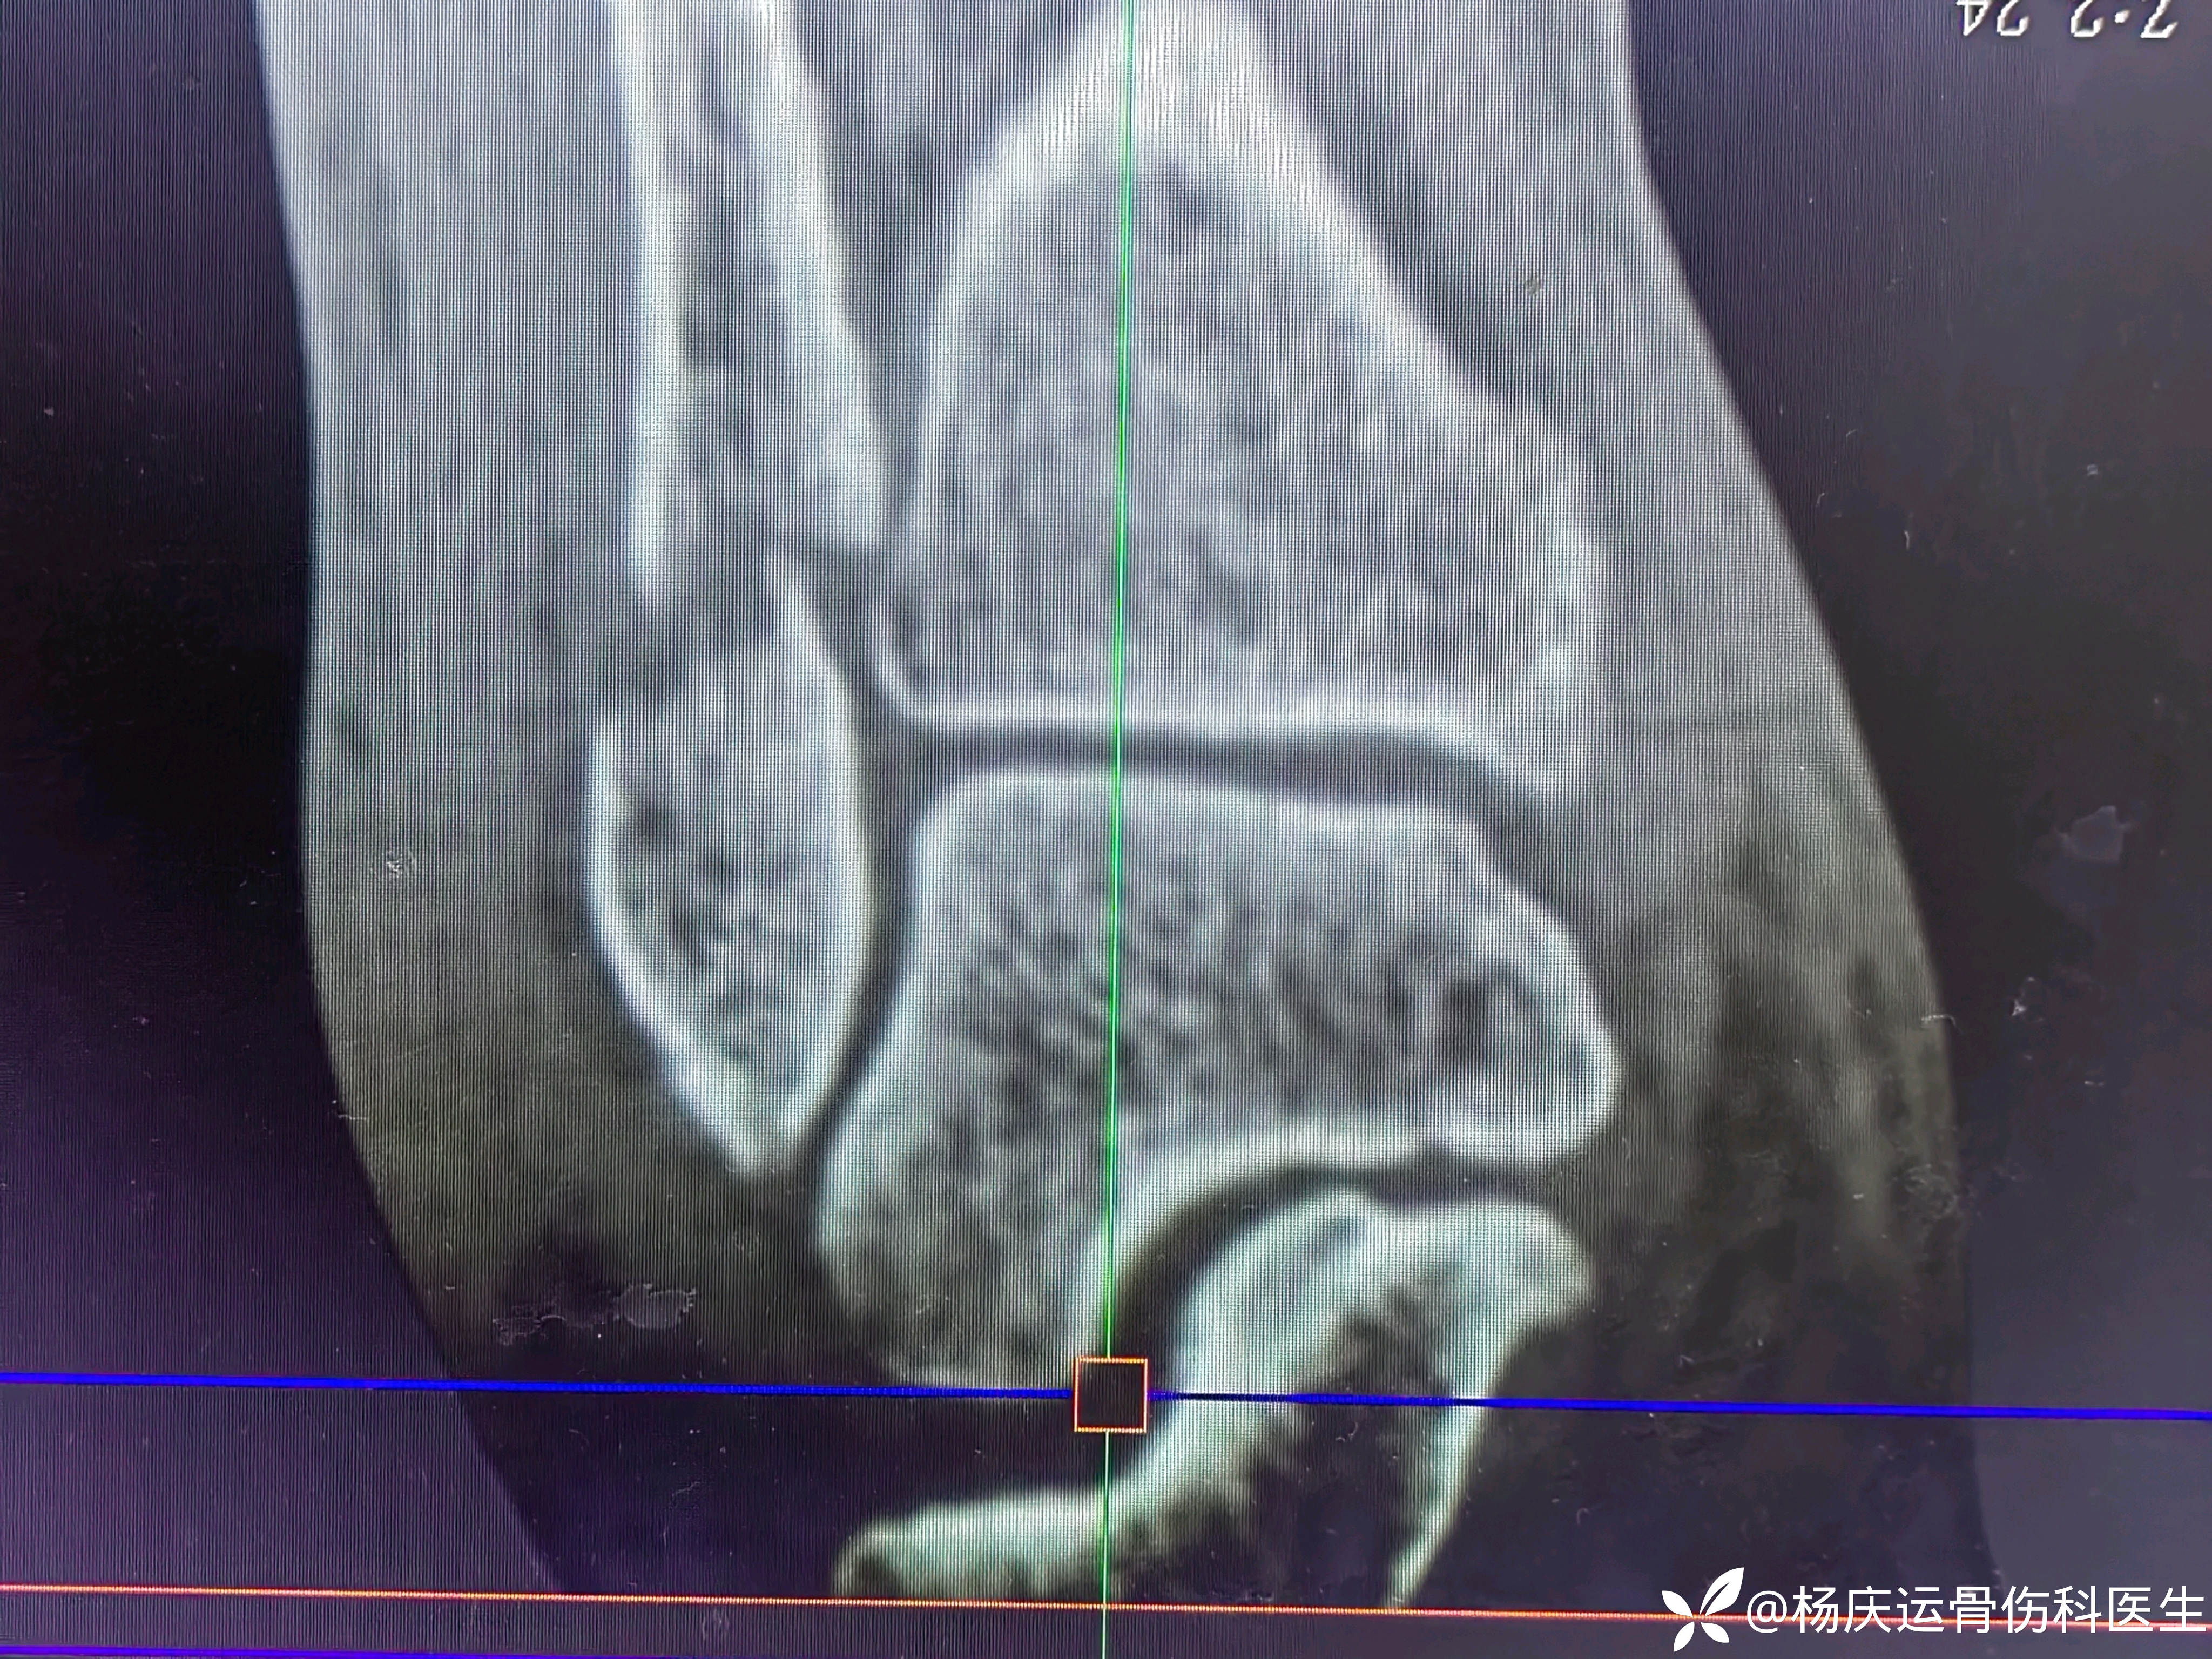

患者矫,女,66岁,左踝扭伤肿痛畸形2小时

初步诊断:左踝关节骨折(L-H分型:旋后外旋型IV)

CT